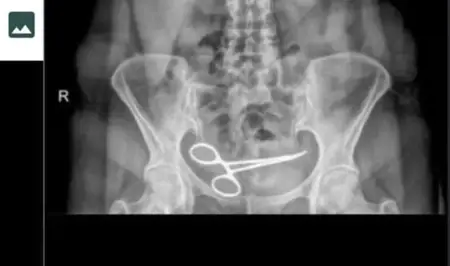

سيدة تركية تكتشف وجود مقص في بطنها بعد 8 أشهر من إجراء عملية جراحية

تقدمت سيدة تركية إلى مستشفى بشكوى من آلام شديدة...